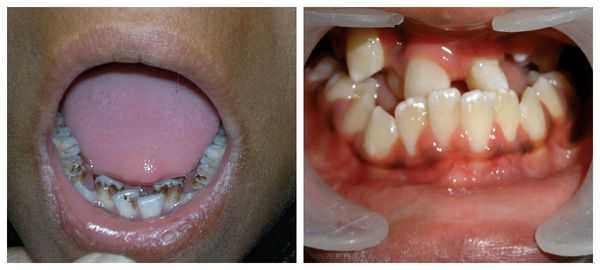

Заболевание проявляется с рождения, у ребенка обнаруживают множественные лентиго — пигментные пятна темно-коричневого цвета размером от нескольких миллиметров до 1 см. При болезни Пейтца-Егерса они преимущественно располагаются на губах и слизистой оболочке ротовой полости, второй по частоте локализацией является промежность (на наружных половых органах и вокруг анального отверстия). Изредка пятна выявляют на нижних конечностях. У некоторых пациентов пигментация исчезает самостоятельно после периода полового созревания.

Синдром Пейтца-Егерса (англ. Peutz-Jeghers syndrome) или гамартомный полипоз желудочно-кишечного тракта (ЖКТ) — орфанное (Запруднов А.М.) заболевание, характеризующееся множественными доброкачественными полипами (гамартомами) в желудке, тонкой и толстой кишке и, одновременно, пигментными пятнами тёмно-коричневого цвета, круглой или овальной формы, диаметром от 1 до 5 мм, располагающимися обычно на коже лица, вокруг рта и глаз, на носу, реже на конечностях, на слизистой оболочке полости рта, иногда гениталий и прямой кишки.

Меланиновая пигментация губ и слизистой оболочки щёк при синдроме Пейтца-Егерса (Кайбышева В.О. и др.)